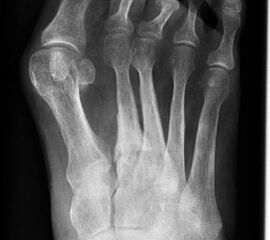

Die Plantarfasziitis ist eine degenerative Erkrankung des Ursprungs der Plantaraponeurose am Tuber calcanei. Das Vorhandsein eines knöchernen Fersenspornes beschreibt dabei zunächst eine radiologisch sichtbare Veränderung, ist aber nicht zwingend mit einer Plantarfasziitis verknüpft 1920.

Ein Röntgenbild der Ferse seitlich ist zum Ausschluss knöcherner Pathologien hilfreich.

Das Behandlungsergebnis wird nicht durch das Vorliegen eines knöchernen Fersensporns beeinflusst 19.

Die distale Insertionstendinose der Achillessehne kann durch lokal entzündliche Prozesse/Mikrorupturen am Verankerungspunkt zur Ausbildung eines dorsalen knöchernen Fersenspornes führen. Dabei liegt die Prävalenz dorsaler Fersensporne bei achillären Insertionstendopathien bei etwa 6-8% (Lohrer 2002).

Ähnlich wie bei der Plantarfasziitis ist das Vorhandensein eines dorsalen Fersenspornes nicht zwingend mit Beschwerden verknüpft und persistiert nach einer ESWT-Therapie.